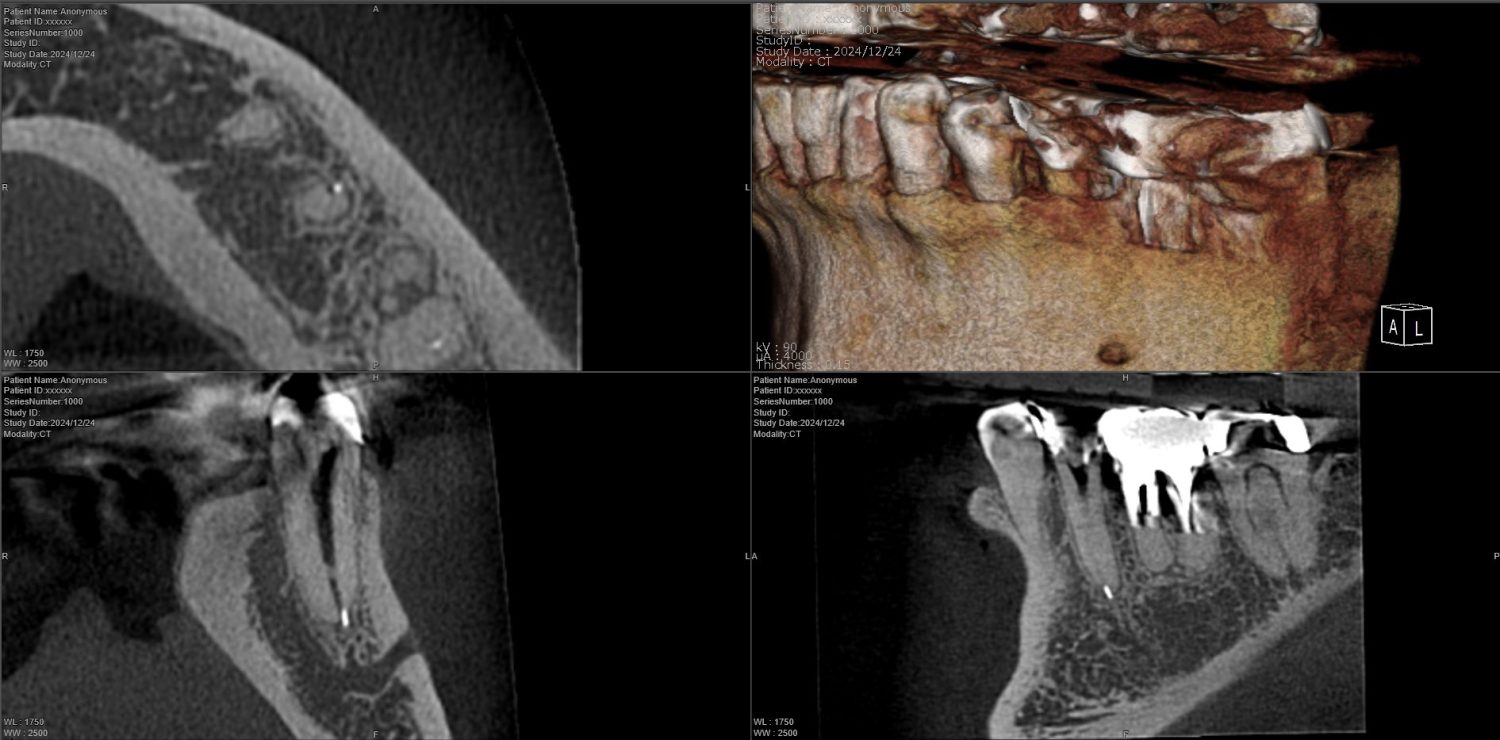

| 主訴 | 過去の治療にて根管充填後、噛むと違和感・痛みが出てきた。一度詰めた薬を撤去してもらったが症状が変わらなかったため来院。 |

| 治療内容 | ラバーダム防湿を行い、マイクロスコープにて根尖部の溢出ガッタパーチャの除去を行いました。 |

CT撮影により根尖部にガッタパーチャの溢出を確認。

拡大視野下にて残存ガッタパーチャを確認しながら過拡大に注意しながら除去。

その後根管充填を行った症例です。ガッタパーチャ除去したことで症状が改善されました。